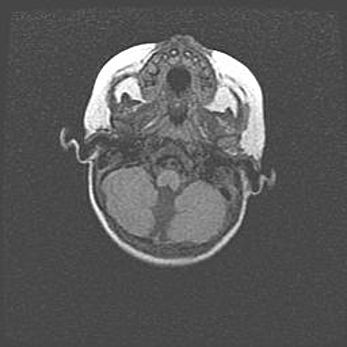

Подострая гематома правой гемисферы мозжечка.

Наружная гидроцефалия.

Возраст: 15 дней

Вес: 3100 г

Пол: женский

Окружность головы: 37 см

Срок гестации: 35-36 недель

При открытой наружной форме гидроцефалии у новорожденных расширяются и переполняются субарахноидные пространства.

Кровоизлияния в мозжечок имеют две клинико-анатомические формы: полушарные гематомы и кровоизлияния в червь.

К появлению этой патологии может привести: повреждения головного мозга, возникающие в результате асфиксии и гипоксии плода при беременности, или травмы во время родов. Редко гематома мозжечка может быть результатом первичной коагулопатии и сосудистой мальформации, диссеминированном внутрисосудистом свертывании, изоиммунной тромбоцитопении.